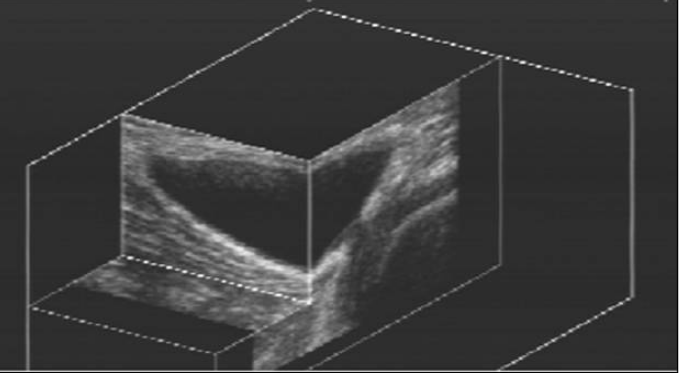

3D ultrasonografické vyšetřování pohybového aparátu

autor: Jakub Jindra | Zář 25, 2025 | Sekce muskuloskeletální ultrasonografie

Hrazdira Luboš1, Skotáková Jarmila2 Ortopedická klinika FN U Svaté Anny, Brno1 Klinika dětské radiologie, FN Brno, Pracoviště dětské medicíny2 Prezentace – 3D echographic examination of the locomotive apparatusStáhnout prezentaci k článku Abstract: Purpose of...